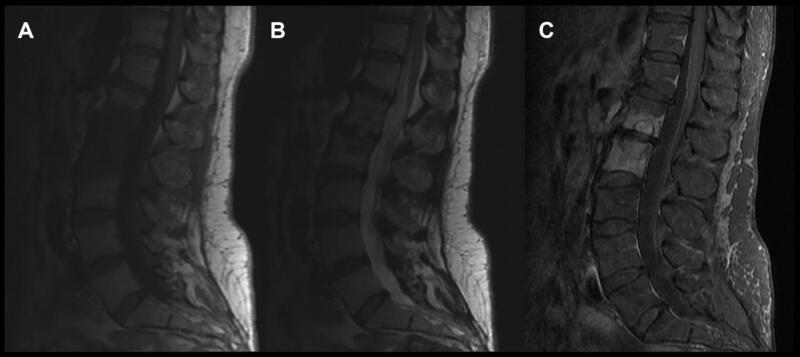

Viêm xương đốt sống có thể xảy ra và thường liên quan nhiều đốt sống và đĩa đệm, tình trạng nhiễm khuẩn lan qua nhiều đĩa đệm đến thân đốt sống (hình 2). Xử trí ban đầu bao gồm sinh thiết để nuôi cấy xác định chủng vi khuẩn, cấy máu, và kháng sinh theo kinh nghiệm trong khi chờ kết quả nuôi cấy. Những BN này thường có tình trạng nhiễm khuẩn xương đáng kể, và cần được phẫu thuật để loại bỏ tổ chức nhiễm khuẩn. Cột sống mất vững có thể là hậu quả của tình trạng nhiễm khuẩn hoặc do phẫu thuật loại bỏ tổ chức nhiễm khuẩn. Do tình trạng nhiễm khuẩn đa số xảy ra ở thân đốt sống và đĩa đệm nên đường mổ theo lối trước hoặc lối bên được các phẫu thuật viên ưa thích hơn, vì dễ tiếp cận và làm sạch tổ chức nhiễm trùng, kiến thiết lại cấu trúc cột sống. Đường mổ lối sau hiếm khi được sử dụng trừ khi nhiễm trùng liên quan đến bản sống hoặc cuống cung đốt sống hoặc nếu cột sống quá mất vững và cần làm cứng thêm ở phía sau.

Hình 2. MRI cột sống thắt lưng không và có tiêm Gadolinium cho thấy hình ảnh viêm xương tủy xương ở L1 và L2. Mô nhiễm khuẩn đồng tín hiệu trên T1 (A), tăng nhẹ tín hiệu trên T2 (B) và bắt tương phản sau tiêm Gado (C).